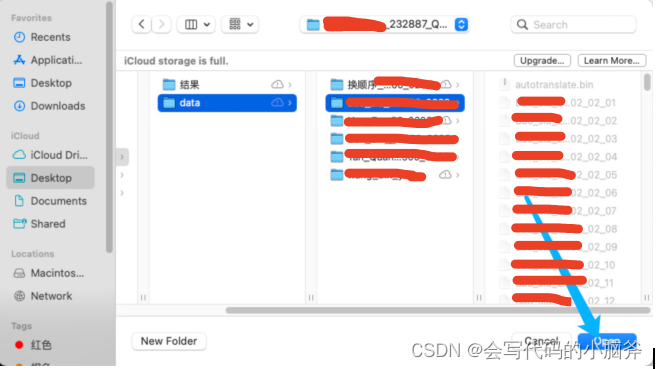

- 导入数据: